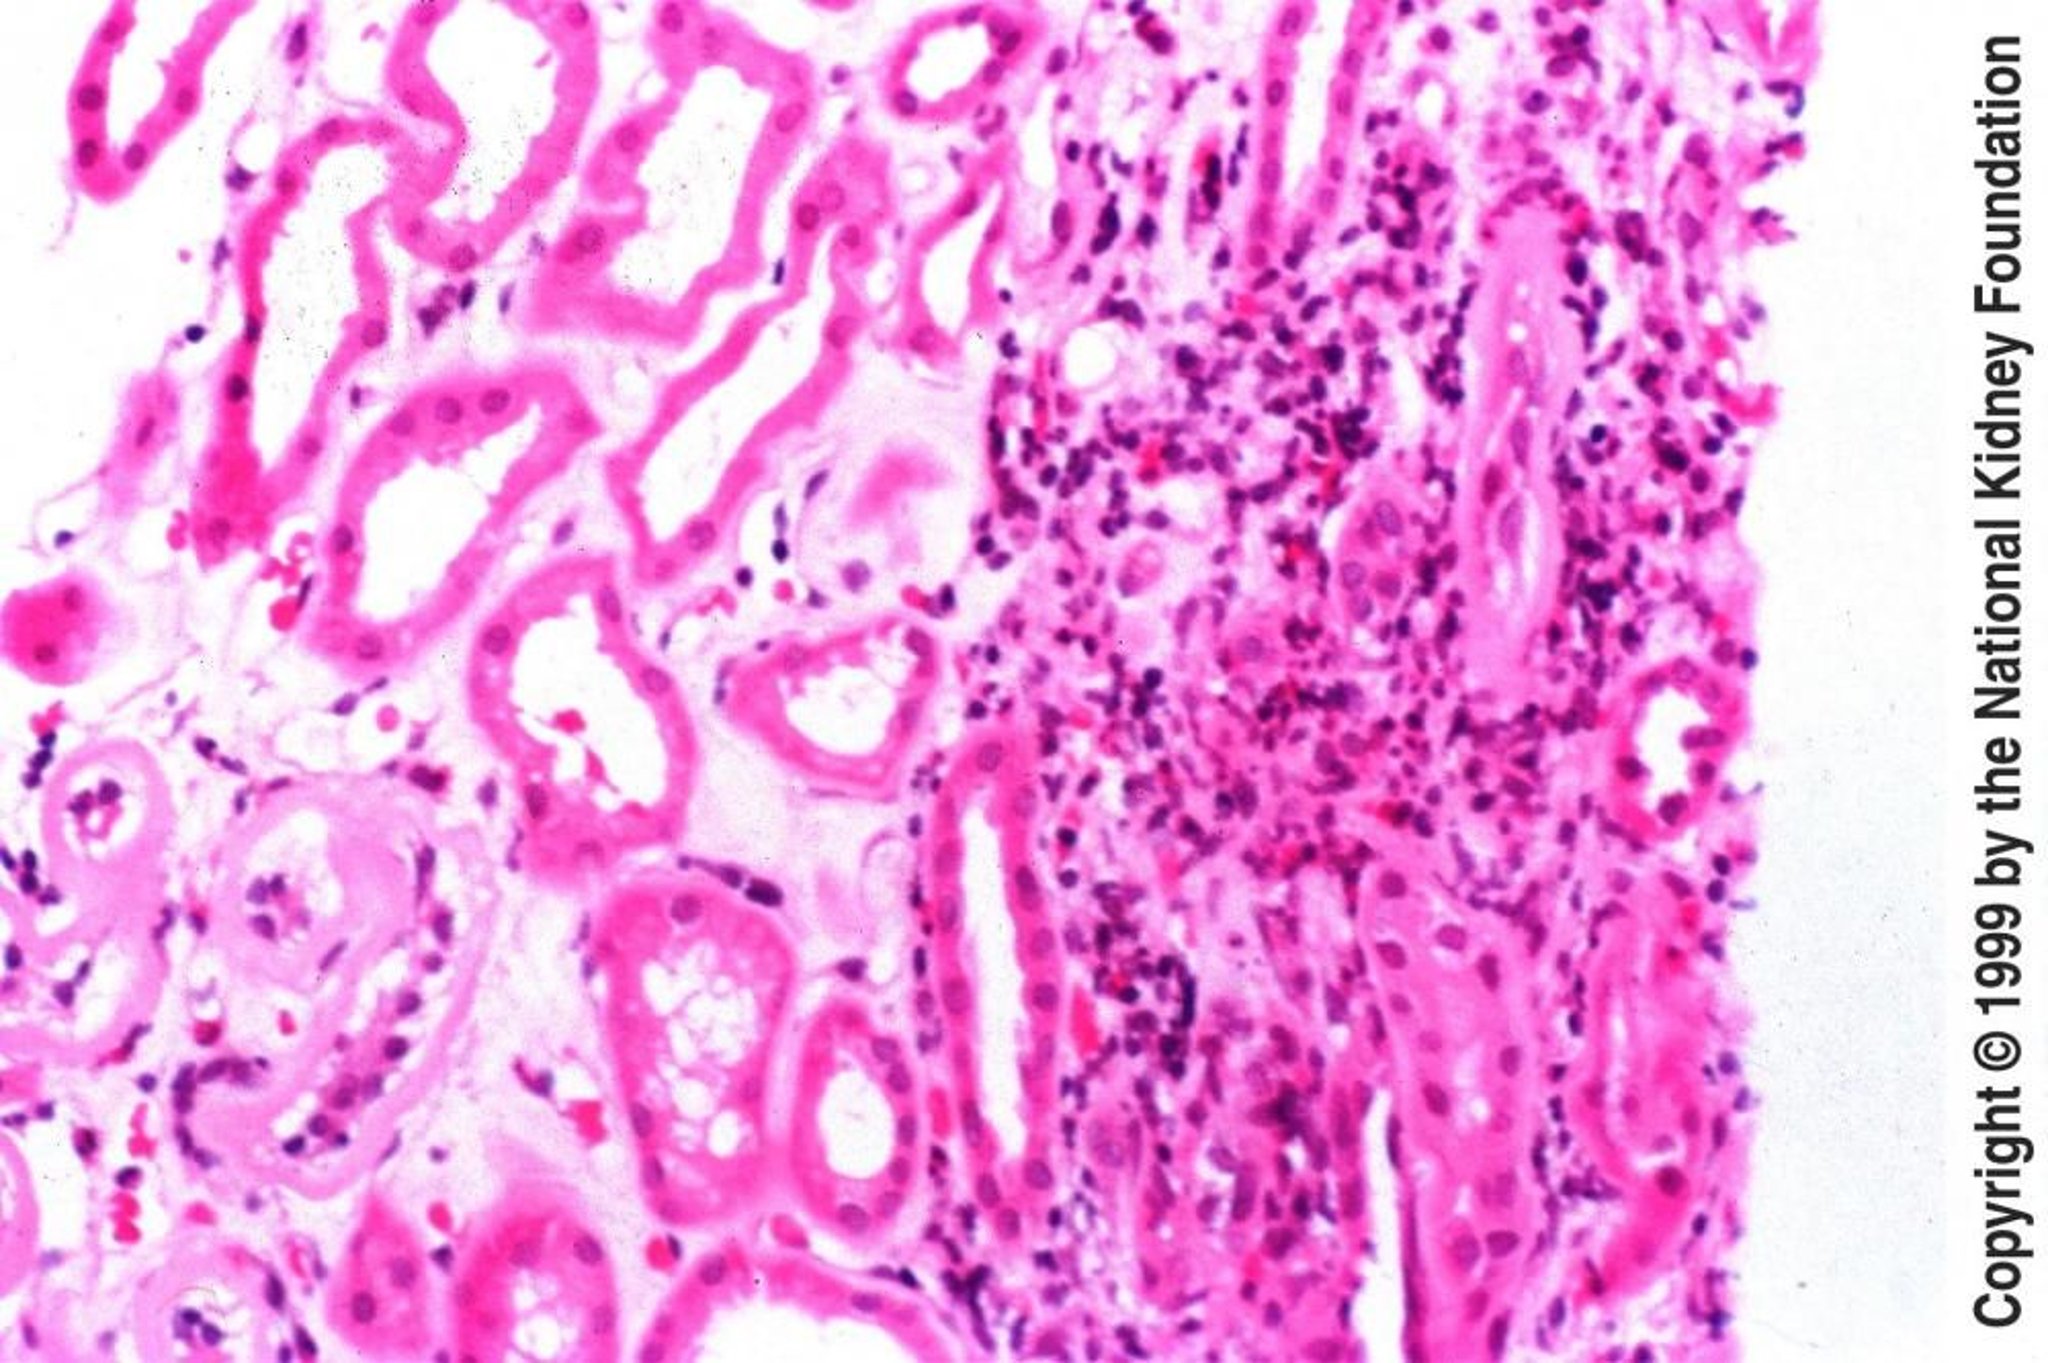

急性尿細管間質性腎炎では通常,糸球体は正常である。最も早期の所見は間質の浮腫であり,典型的にはリンパ球,形質細胞,好酸球と少数の多形核白血球による間質浸潤がそれに続く。重症例では,尿細管基底膜の内側を覆う細胞間の空間への炎症細胞の浸潤が認められ(尿細管炎),その他の検体においては,β-ラクタム系抗菌薬,スルホンアミド系薬剤,抗酸菌,真菌に対する曝露によってもたらされた肉芽腫性反応が認められることもある。非乾酪性肉芽腫の存在はサルコイドーシスを示唆する。腎間質に花筵状線維化(storiform fibrosis)を伴うリンパ形質細胞浸潤が認められる場合は,IgG4関連尿細管間質性腎炎が示唆される。蛍光抗体検査または電子顕微鏡検査では,特徴的な変化を認めることはほとんどない。

慢性尿細管間質性腎炎では,腎生検が診断目的で行われることは多くない。しかしながら,別の診断の可能性が考えられる場合は,検討してもよい。糸球体は正常から完全な破壊まで様々である。尿細管は消失または萎縮している場合がある。尿細管管腔の直径は一様でないが,均一な円柱を伴う著明な拡張を呈する場合がある。間質には様々な程度の炎症細胞と線維化が認められる。非瘢痕域はほぼ正常にみえる。肉眼的に,腎は小さく萎縮している。